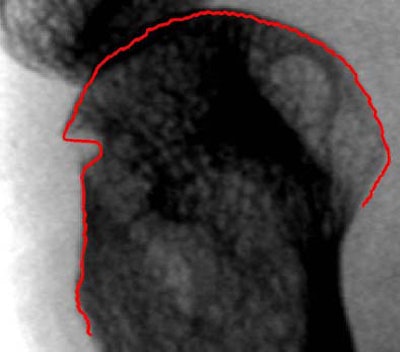

| Above, erosion at fifth MCP joint. Below, red line indicates the result of the automated joint-contour detection algorithm, which adapts also to erosions and fine individual structures of the bone contour. |